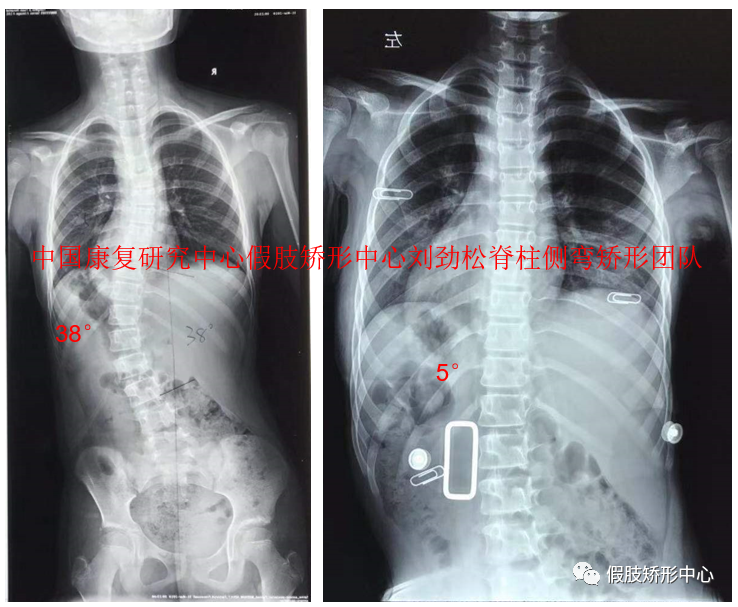

SCS脊柱側(cè)彎矯形器個(gè)案

SCS脊柱側(cè)彎矯形器3D雕刻